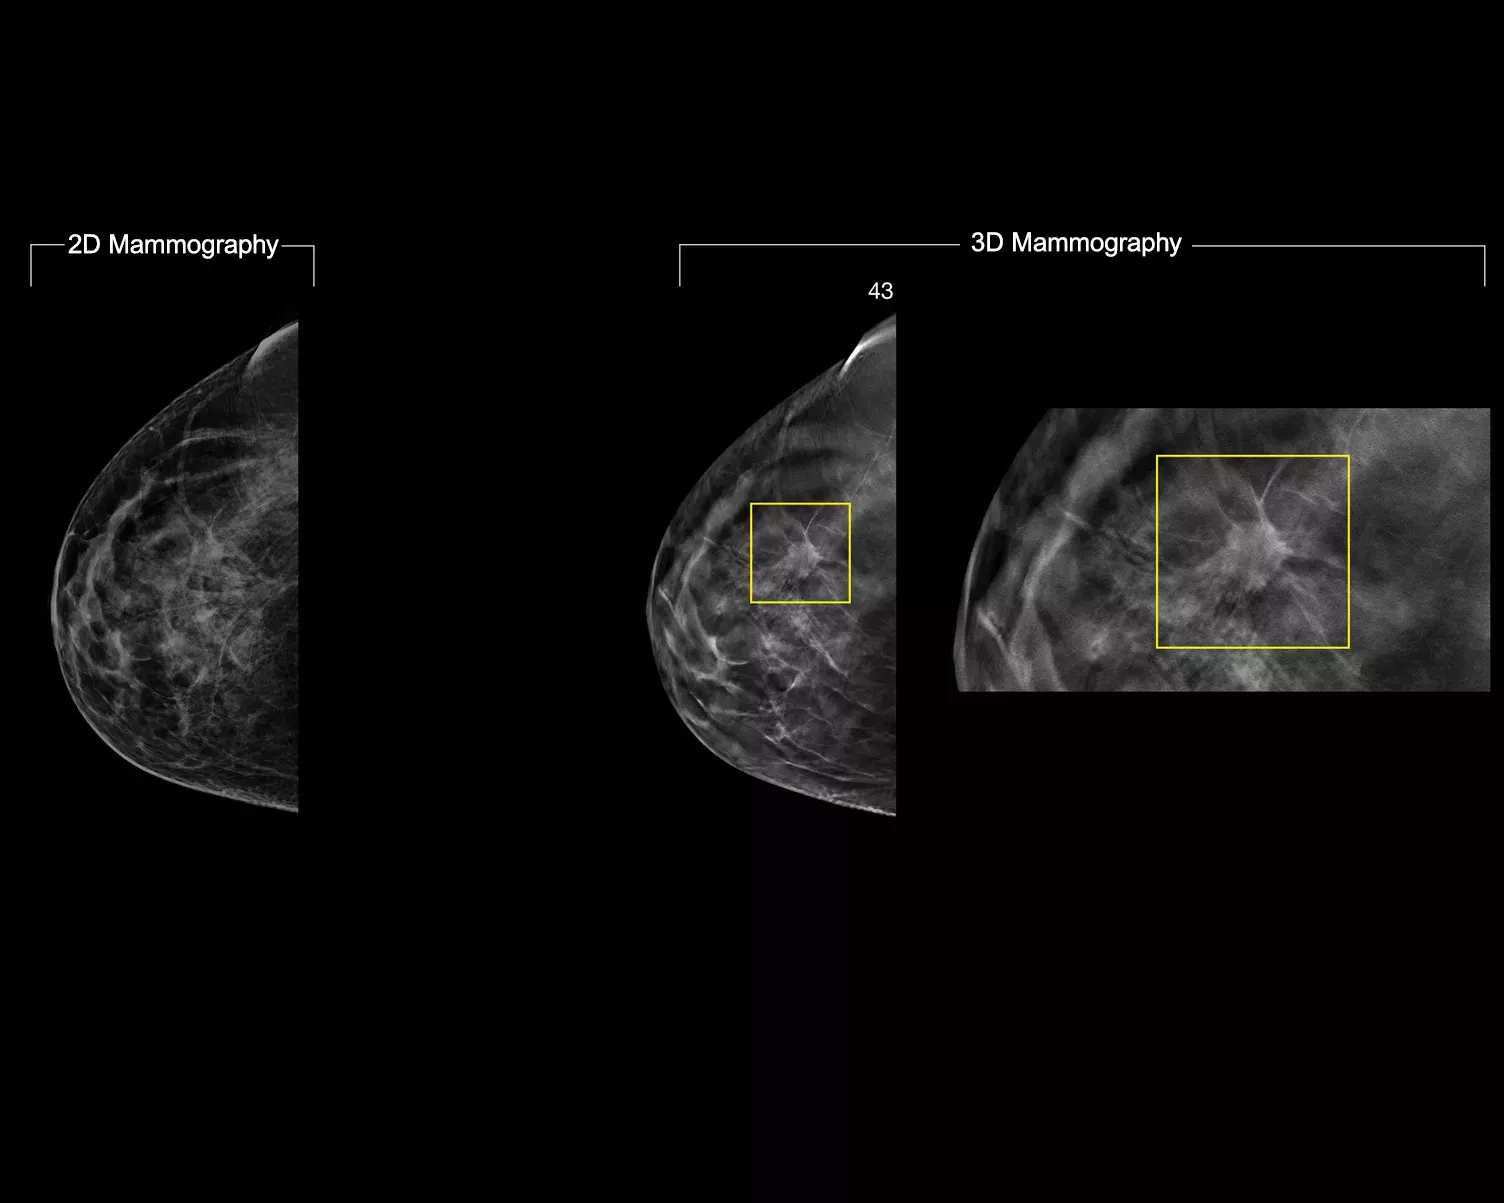

A tecnologia 3DQuorum utiliza análises avançadas com inteligência artificial Genius AI para reconstruir de forma única os dados de mamografia 3D de alta resolução, gerando SmartSlices de 6 mm. Este reduz o tempo de leitura ao reduzir o número de imagens a analisar, sem comprometer a qualidade, a sensibilidade ou a precisão da imagem.2,3 Com a nossa mais recente inovação, pode reduzir os tempos de leitura numa hora por dia.2,3* Aprovado pela FDA para substituir a leitura de cortes de 1 mm.4

A análise Genius AI™ identifica as regiões de interesse e preserva características importantes durante a criação dos SmartSlices.2 A sobreposição de 6 mm com 3mm dos SmartSlices garante que não há perda de dados e assegura a continuidade da deslocação de imagens.5-7

Ao fazer a leitura com SmartSlices em vez de lâminas com 1 mm, o número de imagens 3D™ a analisar reduz em dois terços.5-7 Isto permite poupar, em média, 1 hora por dia no tempo de interpretação de imagens.3